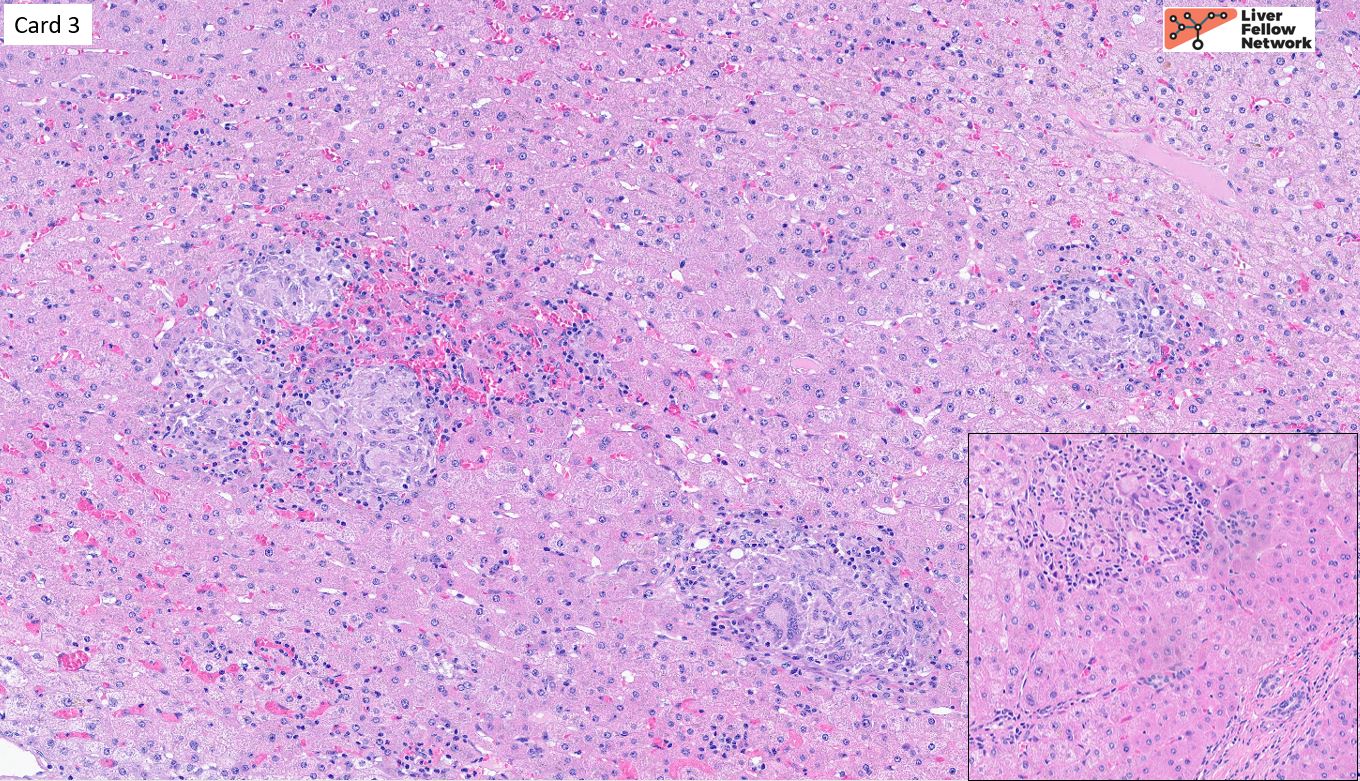

Card 3:

65-year-old patient with decompensated cirrhosis. Alkaline phosphatase is moderately elevated (to 280 U/L); AST and ALT are within normal limits. History is further notable for chronic dyspnea. CT chest demonstrates hilar and mediastinal lymphadenopathy as well as peribronchial thickening. The patient undergoes orthotopic liver transplantation. What is the key histopathologic finding in this image and the associated differential diagnosis?

Correct Answer:

This section demonstrates prominent non-necrotizing epithelioid granulomas scattered throughout the hepatic parenchyma. Granulomatous liver disease prompts a broad differential (see Pathology Pearls post) that includes infection (generally associated with necrotizing granulomas, unlike the non-necrotizing granulomas seen in this instance), drug-induced liver injury (DILI), biliary disease (particularly primary biliary cholangitis), and sarcoidosis. In this instance, the presence of non-necrotizing hepatic granulomas and elevated alkaline phosphatase in a patient with a history of pulmonary disease and hilar lymphadenopathy is strongly suggestive of sarcoidosis. The granulomas in hepatic sarcoidosis are classically portal/periportal, as seen in the inset, and may be highly fibrotic (not appreciated here).